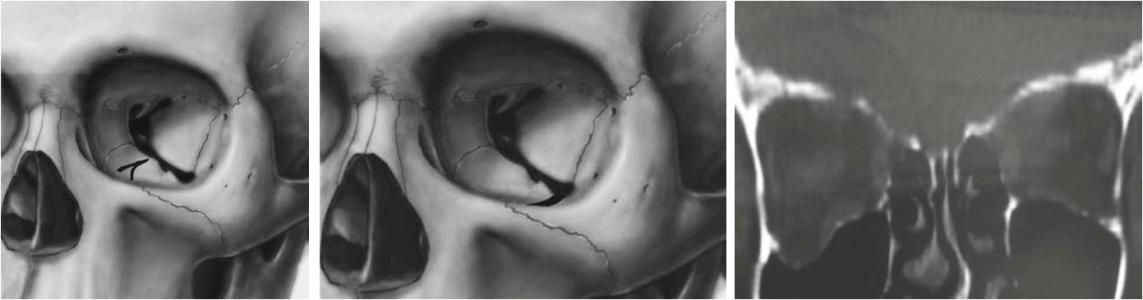

1.眶下壁骨折

是爆裂性骨折最多见的部位。16岁以下患者多为下壁。眶下沟较为薄弱,下壁骨折位置多在此处.或在眶下沟的两侧。虽然眶内壁筛骨纸板比下壁更薄,由于年龄小,眶内壁富有弹性,在外力作用时易产生变形,而不至骨折发生。随着年龄增加,内壁骨折机会增加。

2.眶内壁骨折

筛骨纸板也是爆裂性骨折多见部位,可以是单纯眶内壁骨折,骨折也可在眶内下角,包括筛骨纸板及上颌窦内侧部分。成年人眶内壁弹性减弱,其内壁最薄,平均0.2~0.4mm,是其好发爆裂性骨折的解剖因素。